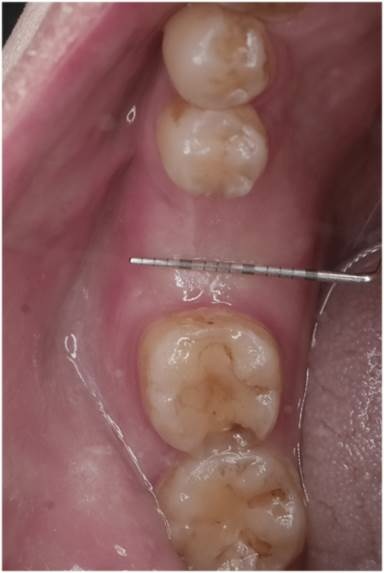

L小姐原本的假牙已經都露出黑邊,

而且全口牙齒顏色都不均勻,讓她自信心大減。